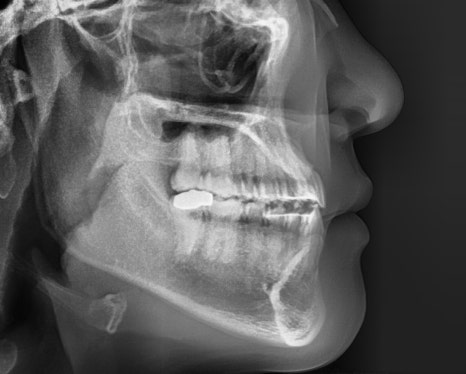

치료결과

실제 소요 기간 : 14개월

반대교합과 불규칙한 치아배열,

아래턱 돌출 등의 문제사항이

확연히 개선된 것을 알 수 있습니다.

예상 교정기간이 24개월이었으나

빠른 치아의 이동으로

10개월 단축된 14개월만에

빠르게 교정을 완료하였답니다.

아랫입술이 뒤로 들어가고,

반대교합이었던 앞니가

정상교합으로 자리잡은 것을

확인할 수 있습니다 :)